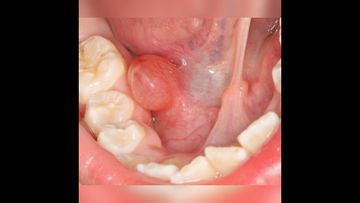

The cyst of the salivary gland is soft, mobile, similar to a tumor

OVIdental Go

Клиническое видео